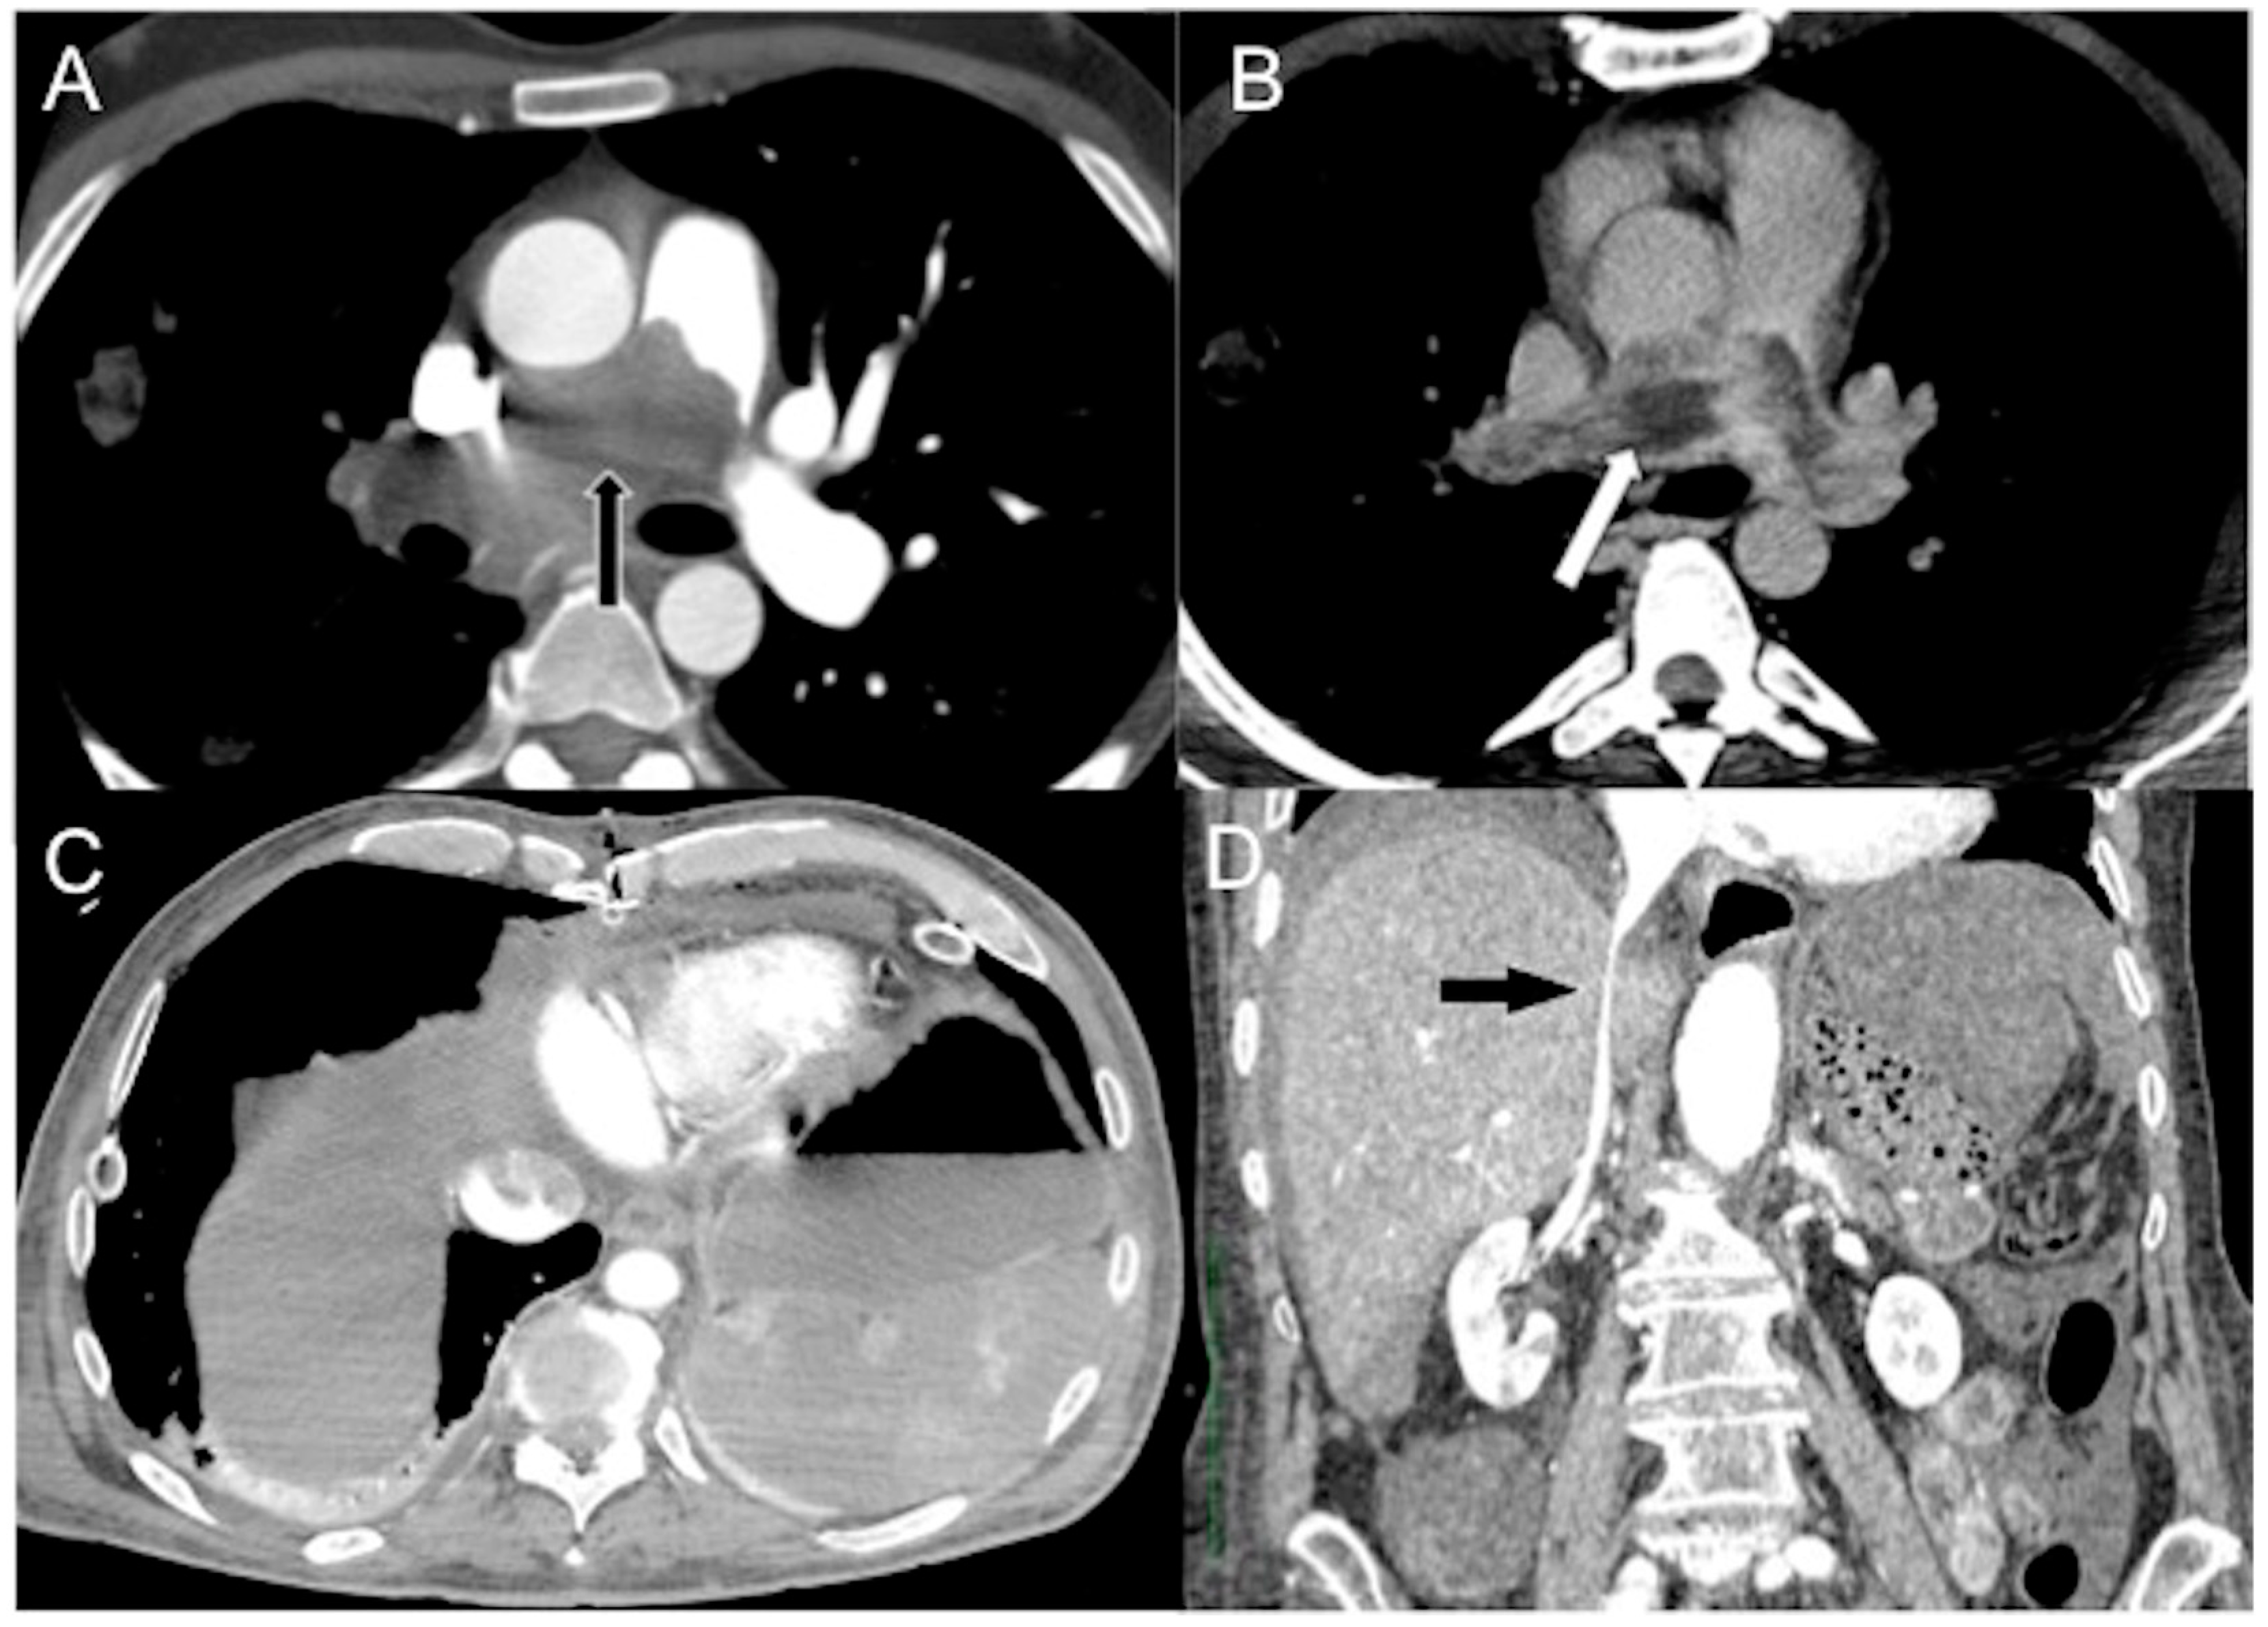

Figure 2. CECT axial images of vascular findings in the four subtypes of hypovolemic shock. (A) Slit-like IVC (arrow) in massively bleeding enteric infarct (hemorrhagic non-traumatic shock). (B) Small caliber hypoenhanced aorta (arrow) in a 32-year-old man wounded by several gunshots, who died twenty minutes after CT examination (traumatic hemorrhagic shock). The characteristic feature of hemorrhagic and traumatic hemorrhagic shock is bleeding. (C) Flat IVC (black arrow) and ascites in a 57-year-old man with decompensed liver cirrhosis and critical reduction in circulating plasma volume (hypovolemic shock in the narrower sense). (D) Flat IVC with halo sign (white arrow) in a 45 year-old firefighter burned with lung toxicity and significant fluid loss (traumatic hypovolemic shock). - Flattening of the IVC (slit sign) is often seen in cases of decreased circulating blood volume (hypovolemia) and indicates reduced venous return in patients with systemic hypotension. However, it may not be easily appreciated due to the administration of large volumes of fluids [31]. This finding is more commonly observed in acute hypovolemic traumatic patients. Variations in intra-abdominal pressure and the respiratory cycle can also affect the diameter of the IVC. IVC flattening has a specificity of 90% and a sensitivity of 84% in identifying hypo-perfusion shock in spontaneously breathing patients [15,16,17,18,19,20,21,22,23,24,25,26,27,28,29,30,31,32,57,58,59,60,61,62,63]. The IVC diameter ratio measured via CT scans can help predict in-hospital mortality in septic shock patients, with a cut-off value of ≥1.3 cm having 75% sensitivity and 42% specificity [63]. It is also useful in determining the amount of blood transfusion required and assessing the volume status of patients with blunt torso trauma. [64].

- The IVC halo sign is characterized by a low attenuation band (<20 HU) encircling the collapsed intra- and retrohepatic inferior vena cava. This band is caused by a ring or rim of edema [65,66,67]. In cases of severe hypovolemia, approximately 80% of patients may exhibit this sign, resulting from the loss of precapillary arteriolar sphincter tone and the accumulation of fluid surrounding the IVC (Figure 2B–D) [18,25,30,31,65,66,67]. However, it is important to note that this sign is not specific to non-traumatic patients and can also be observed in conditions such as liver congestion, biliary cirrhosis, hepatitis, or other diseases that obstruct lymphatic drainage at the porta hepatis [25].

CECT axial images of vascular findings in cardiogenic shock. (A) Portal venous phase (delay of 80 s after CM injection) shows IVC contrast level sign (arrow) as well as heterogeneous hepatic enhancement (asterisk) in a 65-year-old man with myocardial infarction and imminent cardiac arrest. (B) Portal venous phase (delay of 85 s after CM injection) shows IVC contrast level sign (arrow) and regurgitation to the right renal vein (empty arrow) in a 63-year-old man with hypotension and acute severe reduction in cardiac index. In comparison to Figure 1D, note the aorta opacification. (C) Portal venous phase (delay of 85 s after CM injection) shows IVC contrast level sign with CM reflux into hepatic VI and VII segments (empty arrow) and (D) contrast level in portal trunk (arrow) in a 68-year-old man with myocardial infarction.

In contrast to horizontal levelling in the IVC layering sign, a vertical IVC levellng sign usually occurs due to physiological retrograde filling of renal veins [68]. Contrast stasis in the right-side cardiac chambers may result in extremely dense chambers and pulmonary arteries with or without a blood contrast level. Vascular stasis will also result in contrast layering within the veins that eventually drain into the right atrium (e.g., brachiocephalic and subclavian veins) (Figure 4).

Figure 4.

CECT images in obstructive shock in a severely dyspneic 28-year-old man with malignant pulmonary artery sarcoma. Arterial (A) and delayed (B) phase axial images show massive pulmonary trunk (black arrow) and right main artery (white arrow) soft tissue mass obstruction. A more caudal (C) axial image shows CM stasis in right cardiac chambers, no hepatic enhancement, and mild pleuropericardial effusion. (D) Delayed phase (delay of 200 seconds after CM injection) coronal reconstruction shows a thinned flat IVC (black arrow).